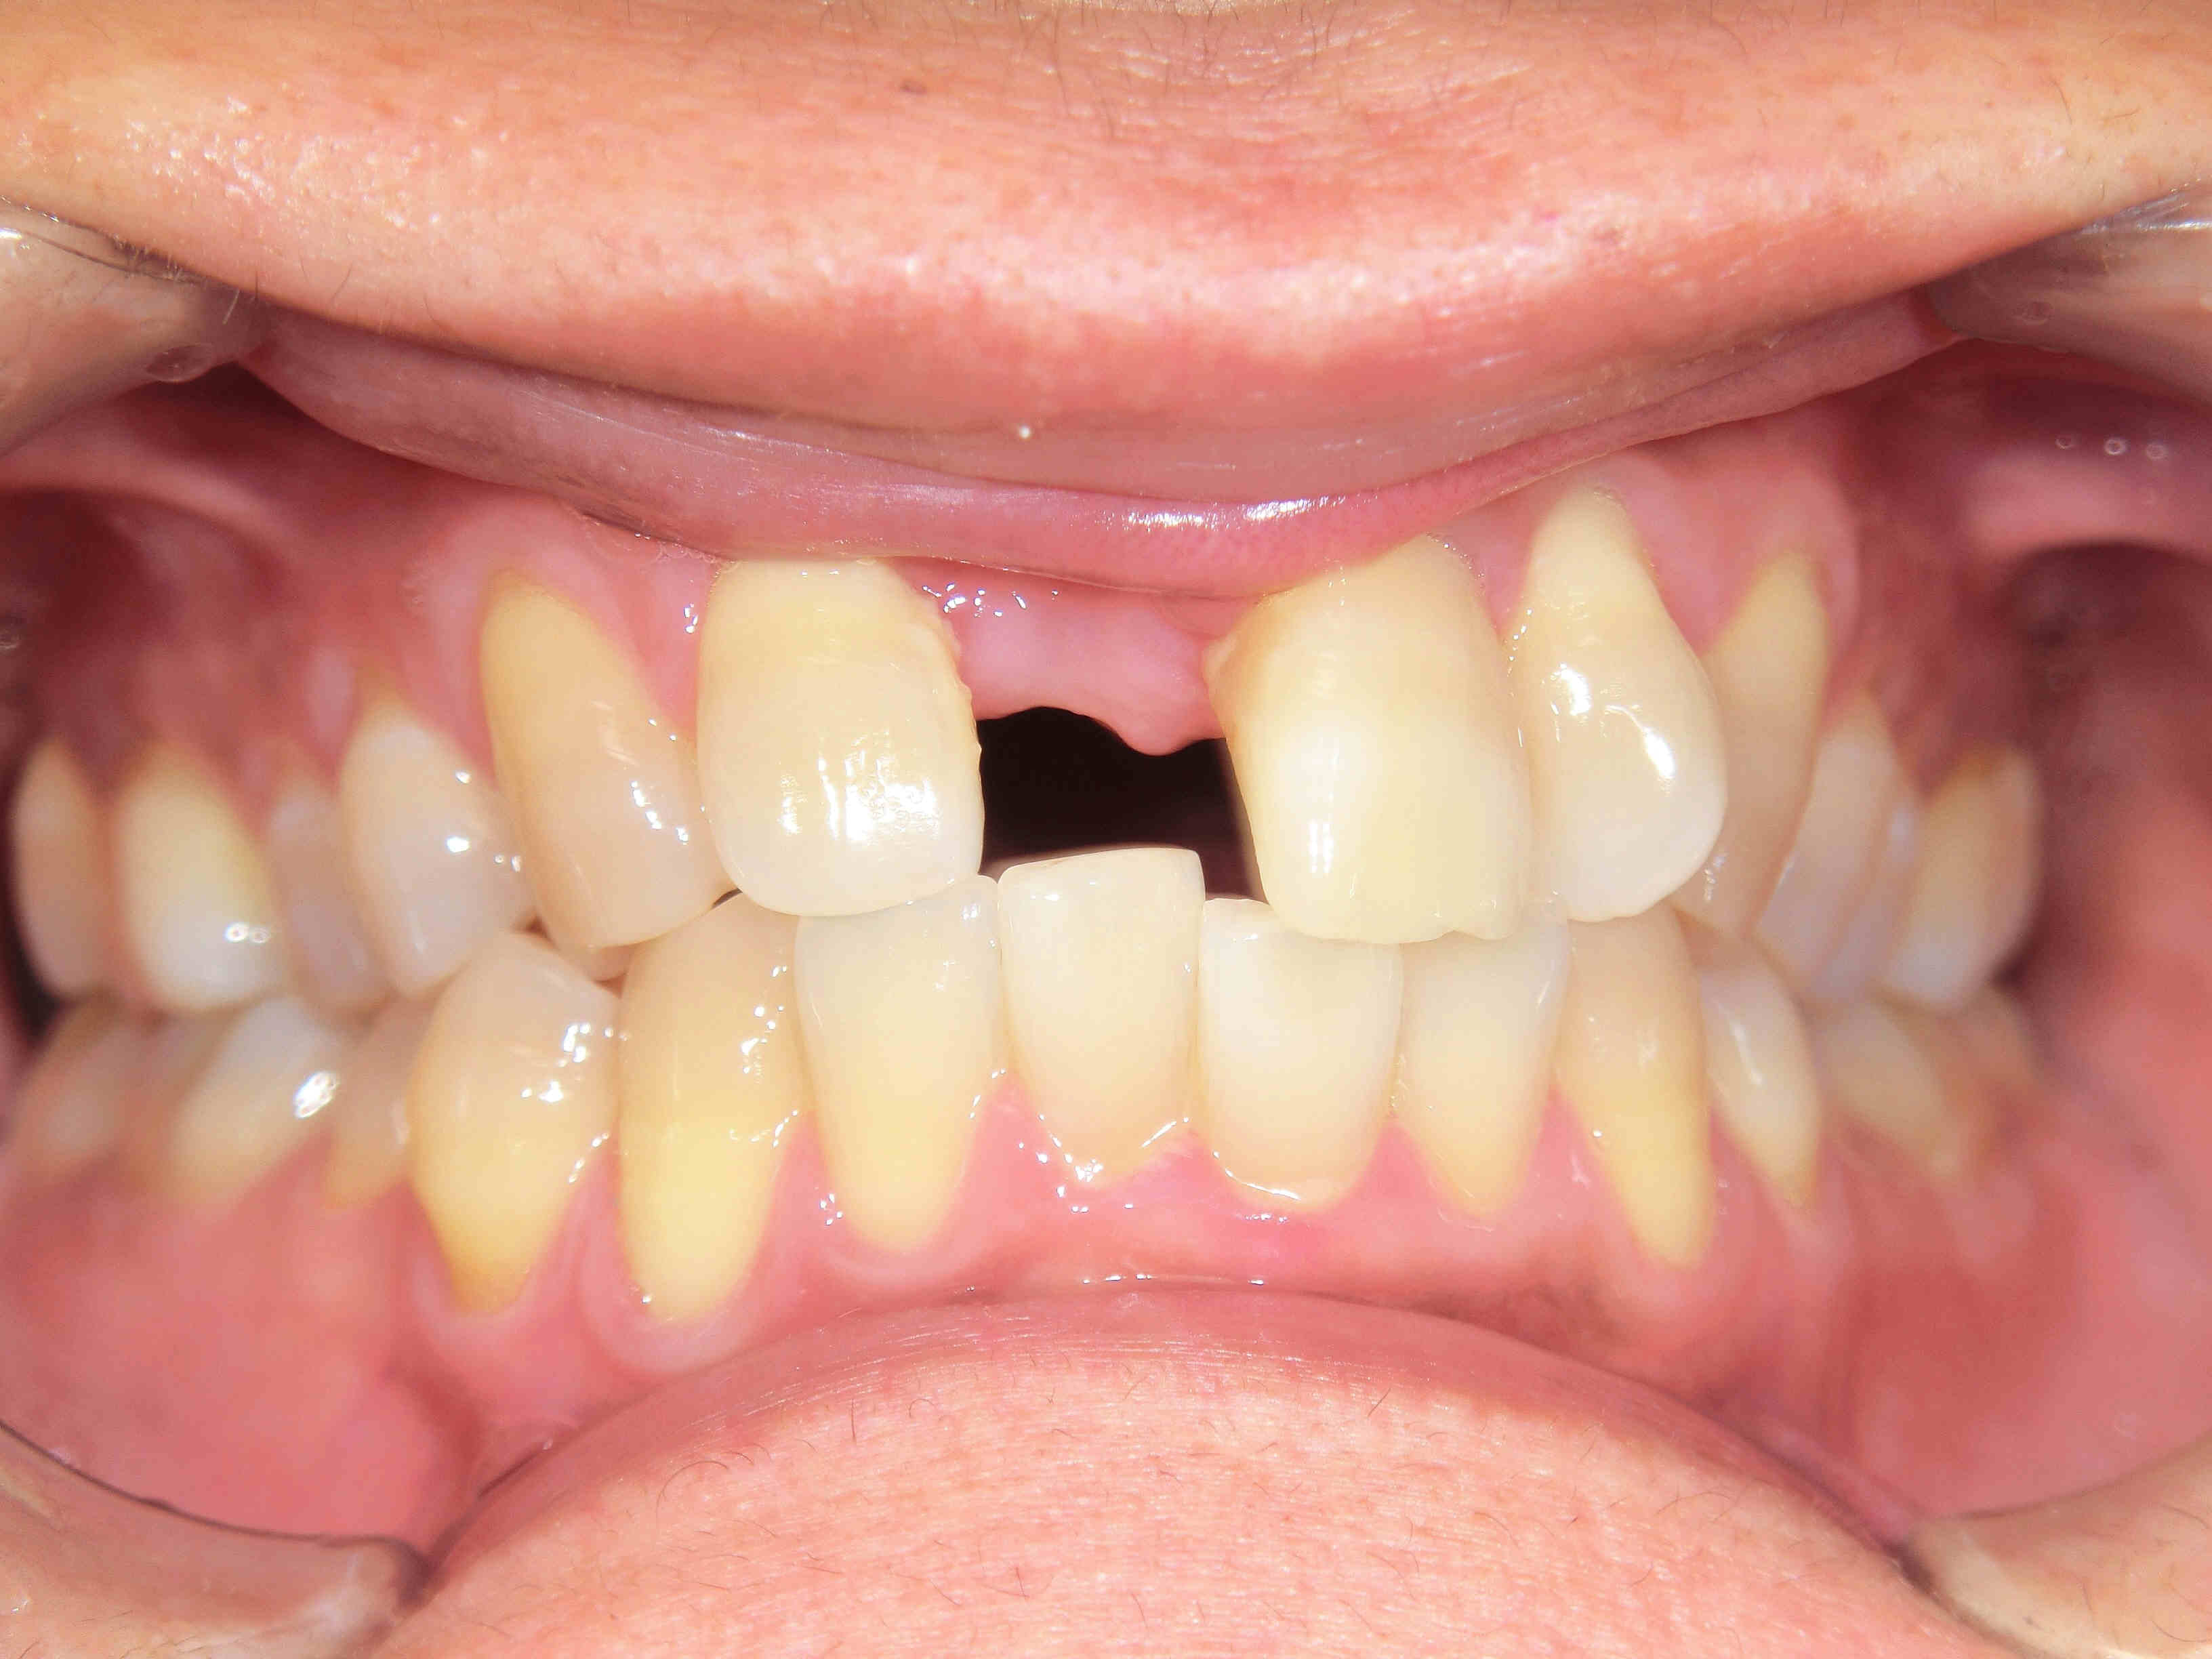

インプラント症例紹介(40代男性/右上前歯)

初診時、右上前歯がグラグラしており、抜歯およびインプラント治療をご希望されました。診査の結果、歯根が骨にほとんど埋まっておらず、保存は困難であったため、抜歯を行いました。

抜歯後は骨の幅が不足していたため、骨造成(GBR)を併用し、約半年後にインプラント治療を行いました。